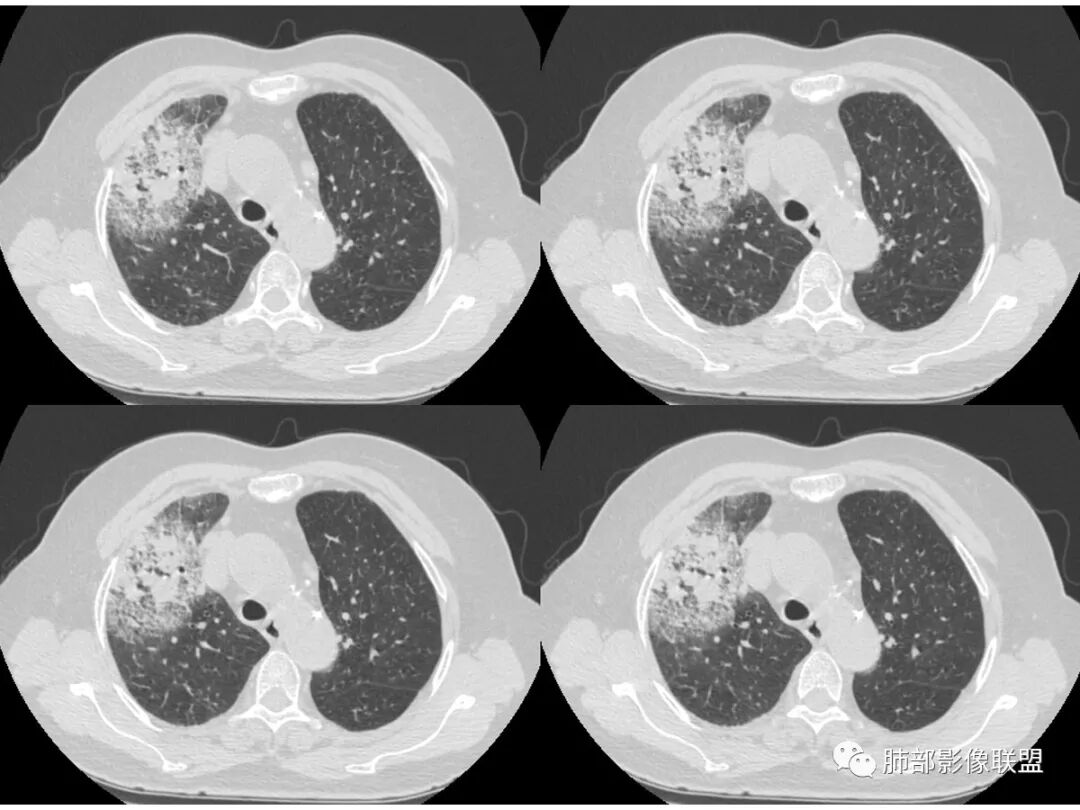

胸CT:右肺上叶实变内可见支气管充气征,近端支气管狭窄,远端扩张,周围可见毛玻璃影,右肺中叶支气管闭塞,并可见气道壁钙化,右肺中叶体积缩小,实变内可见空洞,并可见气液平面,空洞周围可见毛玻璃样影,右肺下叶支气管开口狭窄,右肺门淋巴结肿大。纵隔窗可见病灶与壁层胸膜间隙增宽,考虑良性病变-----感染性病变------TB?

右中叶支气管完全阻塞伴厚壁空洞,右上叶支气管不全阻塞伴大片GGN,右下部分GGN考虑腺鳞癌,结核待排。

老年女性,慢性病程,咳嗽伴白色粘液痰,无发热腹痛,糖尿病,白细胞及C反应蛋白不高,血沉快,铁蛋白高。胸部CT,右肺上叶大片状实变伴磨玻璃密度影,边界不清,边缘局部膨隆,叶裂弧形下坠,实变影宽基底与胸膜相贴;右肺下叶前基底段见类似病灶;右肺中叶不张并空洞形成,空洞内见气液平面;综合考虑右肺上叶及下叶肺炎型肺癌,右肺中叶结核。

老年女性,病史1月,右肺上中叶大片状影,跨叶,上叶为主,磨玻璃为主,边界模糊,部分实变,内见空洞影和液气平面,壁光滑,支气管开口狭窄,局部有扩张,右肺门淋巴结钙化,首先考虑感染性病变,结核可能,鉴别粘液腺癌。

老年女性,亚急性起病,右肺上中叶大片状影,跨叶,上叶为主,磨玻璃为主,边界模糊,部分实变,内见空洞影和液气平面,壁光滑,洞内可见结节形成,局部有扩张,首先考虑感染性病变,结核可能;洞内可见结节样病灶,鉴别合并曲霉、肿瘤。

这里是中叶的不张和空洞,有钙化,结核确实也不能排除

主病灶应该是粘腺腺癌,右中叶不张?,内空洞,壁光滑,考虑感染